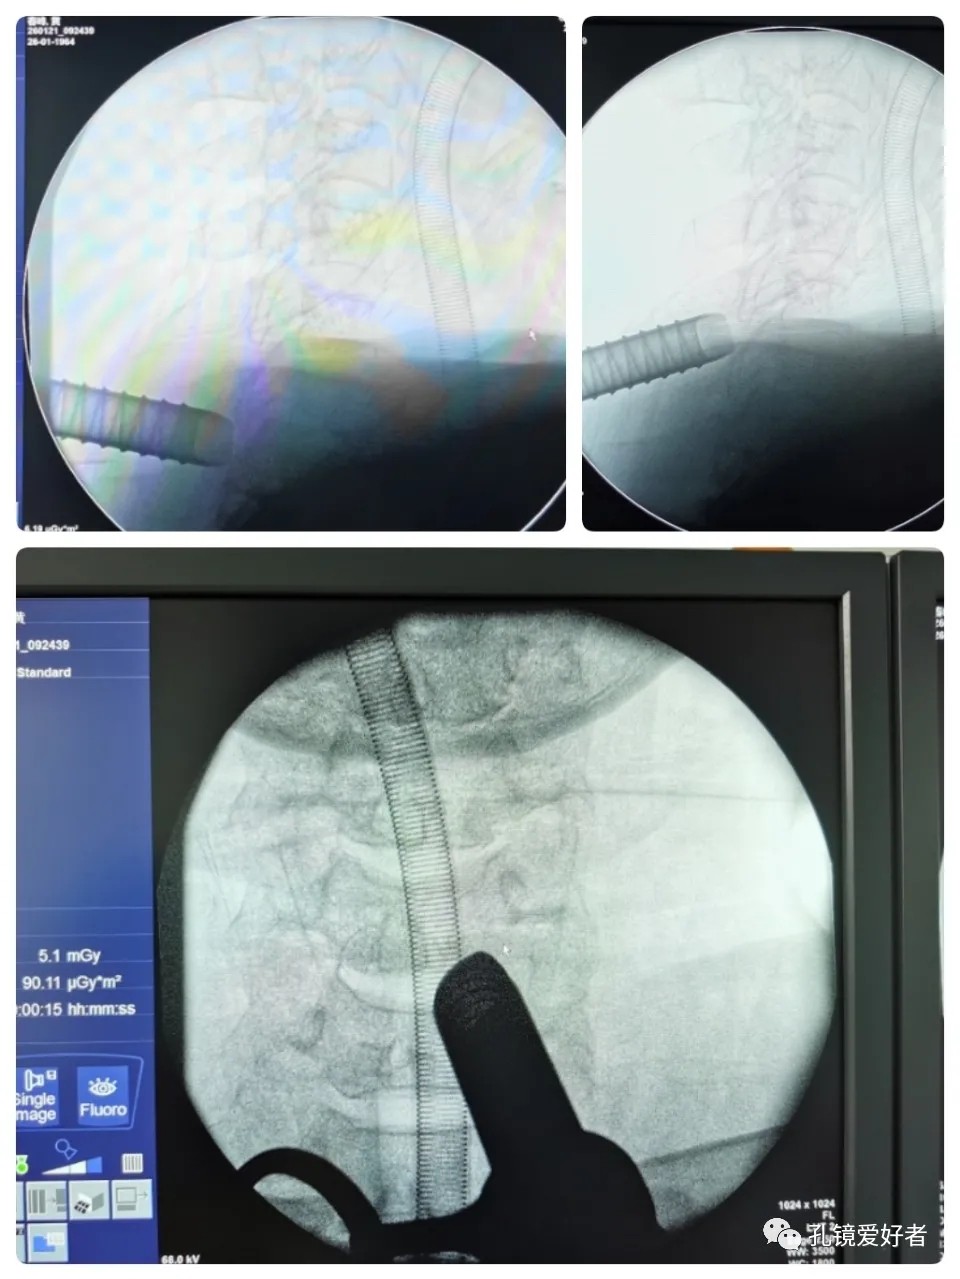

C-arm X-ray

From the AP side, it can be seen that the surgical tool is well placed next to the spinous process, which is not far away. From the lateral side, it can be seen that by moving the surgical tool up and down, it can cross the entire lamina of C6 to reach both the upper and lower spaces of the vertebrae.